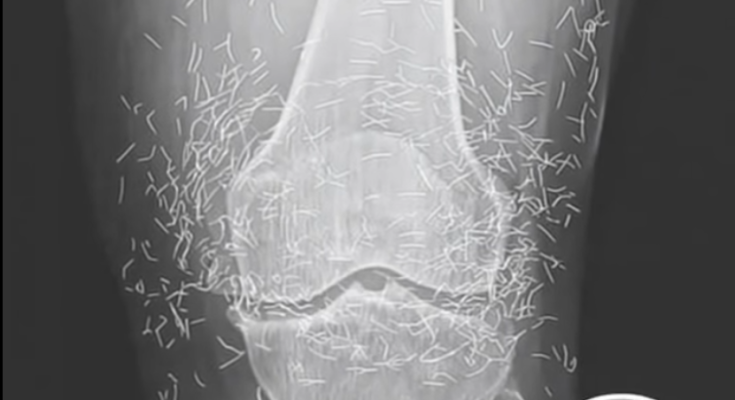

What started as a routine hospital visit for knee pain turned into a medical mystery that left doctors speechless. A 65-year-old woman in South Korea went in expecting a diagnosis of arthritis — but when her X-ray appeared on the screen, the room fell silent. Her knee joint wasn’t just worn down from age; it was filled with dozens of tiny gold needles. The strange discovery sparked immediate questions about how they got there and why they had remained unnoticed for so long.

Doctors soon learned that the woman had been struggling with osteoarthritis for years, a condition that makes everyday movement painful as cartilage breaks down. Frustrated by the limits of conventional medicine, she had turned to acupuncture — a centuries-old therapy believed to ease pain and improve circulation. But instead of using temporary needles, her acupuncturist had inserted fine gold ones beneath the skin permanently, convinced they would provide lasting healing energy.